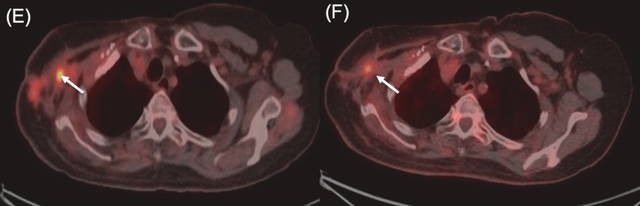

病例3

一名76岁女性,患有三阴性浸润性导管癌。其后出现胸壁和腋窝复发,侵犯臂丛神经并导致右臂完全瘫痪。BNCT治疗后右肩部和皮下病灶消退,仅残留小腋窝结节,2025年11月的随访胸部CT显示,患者照射部位保持部分缓解,局部控制得到改善。